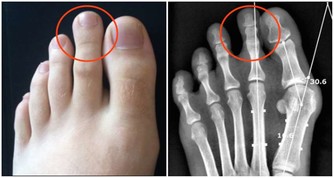

糖友買鞋,建議大半號

建議糖友最好在下午或傍晚去買新鞋,應選圓頭厚底、鞋碼大半號,且有鞋帶或搭扣的鞋子,這樣可方便調節腳的肥瘦情況。

還要注意選寬大、透氣性好的鞋子;鞋底要厚,彈性好,最好是防滑的牛筋底或膠底。

一開始穿新鞋時,千萬別穿太久,每次穿著20~30分鐘為宜。還應檢查鞋內壁和鞋墊上有無褶皺線頭,鞋內有無小石子等異物。